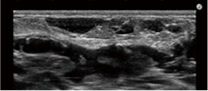

- 事前のエコー検査で異常の有無を確認

- 異常が見つかった場合は即報告&対応

- エコー検査で脂肪の定着をチェック

- 豊胸の成果を視覚化して共有